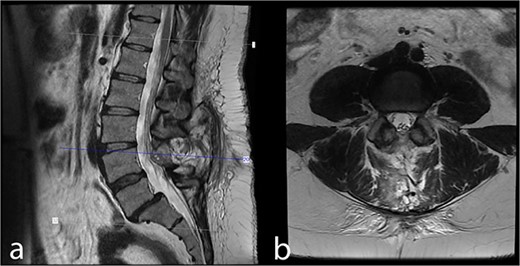

The patient exhibited no neurological deficits after surgery and experienced relief from tailbone pain. In the patient’s 43-month follow-up, she exhibited no symptoms or indications. The control MRI revealed no remnants or recurrence (Fig. 3).

Forty-three month postoperative (a) midsagittal and (b) axial MRI images show no residual/recurrent intradural lesion.